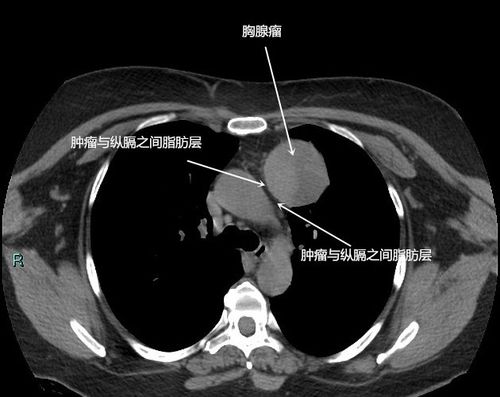

胸腺瘤前纵隔占位前纵隔结节是癌症吗

胸腺瘤/前纵隔占位/前纵隔结节/伴有肌无力是癌症吗?

省立影像读片前纵隔肿瘤2109